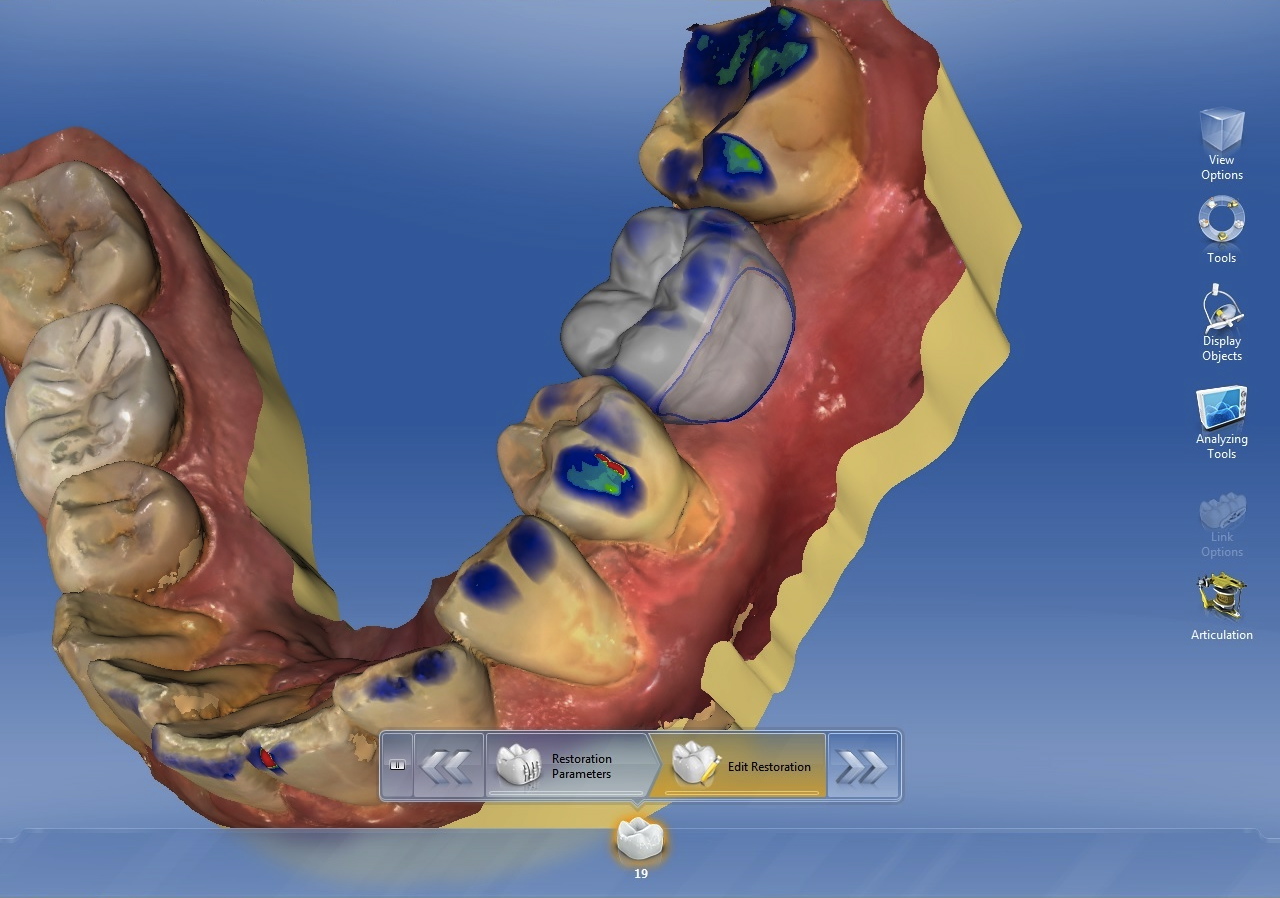

The first step is to design the desired restoration. If designed with CAD/CAM design software (Figure 1), the restoration will need to be saved in a file type that is compatible with the implant-planning software being used. If using an analog wax-up, the waxed up model will have to be scanned with either a laboratory scanner or a chairside CAD/CAM scanner and saved in a compatible file type.

Digitally designed restoration for an edentulous space.

Figure 1